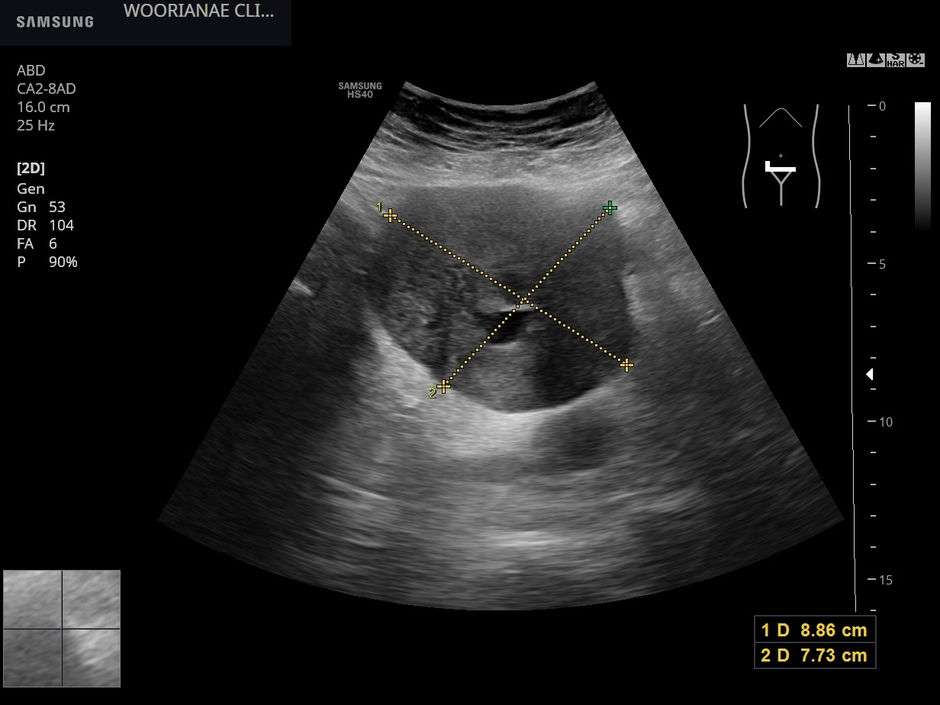

게실염 및 농양의 임상적 추적/초음파 추적 - 동대문구 - 동대문구 답십리, 성수동, 우리안애 우리안愛 내과

https://blog.naver.com/ejercicio/223110439406 상기 환자 5일뒤 외래 괜찮다. 죽먹는데.. 식후 꽉찬 느낌정도 지난 외래 이후 3 kg 빠졌다가 회복 초음파 추적시 압통은 없으며 게실염때 주변부 염증 반응은...